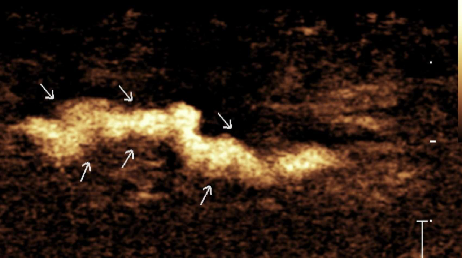

淋巴管超声造影:显著提高淋巴管超声显影率,为淋巴管——静脉吻合提供精准术前定位,也是评估淋巴--静脉吻合术后疗效评估的可靠影像检查方法。

淋巴管造影